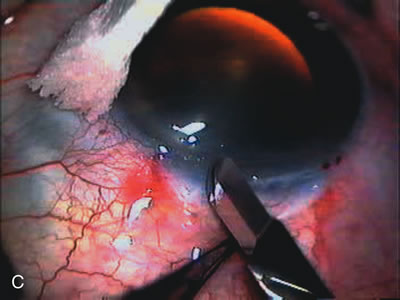

Fig. 1. The anatomic advantage of small incision cataract surgery for the glaucoma patient. A. Long-term bleb function with a large cataract incision is difficult to achieve with either ECCE-trabeculectomy or trabeculectomy followed later by ECCE. This bleb failed to form sufficiently when combined with large incision ECCE. The inflammation, bleeding, and long-term wound healing with stimulation of fibroblasts associated with this technique are more likely to cause bleb failure. In addition, the increased iris manipulation necessary to deliver the nucleus and subsequent iris repair adds to the long-term breakdown of the blood aqueous barrier. B and C. Two-site phacotrabeculectomy has the advantage of small incision cataract surgery combined with separate site trabeculectomy. The incision size is one third the size of the standard ECCE. The inflammation is less severe, and cataract wound healing is confined to the temporal area. Visual rehabilitation with phacoemulsification and foldable IOL is much faster. Phacoemulsification allows successful lens extraction even in the unfriendly environment of a smaller pupil compared with ECCE. The trabeculectomy is performed in an entirely different site, well away from the wound healing associated with temporal phacoemulsification. The likelihood of this filter functioning long-term is greater than with ECCE-trabeculectomy. D. The surgeon also has the option of single-site phacotrabeculectomy with foldable IOL. Both the lens extraction and trabeculectomy are performed through one small 3.5-mm limbal incision.

Fig. 3. Partial bleb failure following clear corneal phacoemulsification with foldable IOL. A. Preoperative bleb appearance prior to temporal lens extraction. Preoperative IOP was 12 mm Hg on no antiglaucoma medications. Time from 5-FU trabeculectomy surgery to lens extraction was one year. B. Bleb appearance 2 months after clear corneal cataract surgery with topical anesthesia. Following lens extraction, increased vascularity was noted along with decreased size of the filtering bleb. IOP increased to 20 mm Hg as early as 2 weeks after surgery, necessitating topical antiglaucoma therapy. C. High magnification view of bleb before lens extraction demonstrates diffuse pale bleb. D. High magnification view of bleb 2 months after surgery. There are vessels surrounding the nasal side of the bleb and the overall bleb size is smaller.